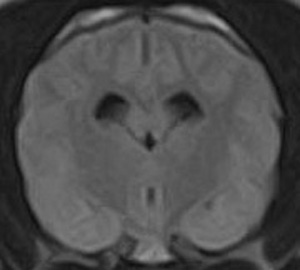

市内の先生からけいれん発作が出るとのことでMRI検査の依頼がありました。検査では脳に構造上の異常を認めず、脳脊髄液検査も問題なく、特発性てんかんとの診断でご紹介もとの病院様での治療となりました。